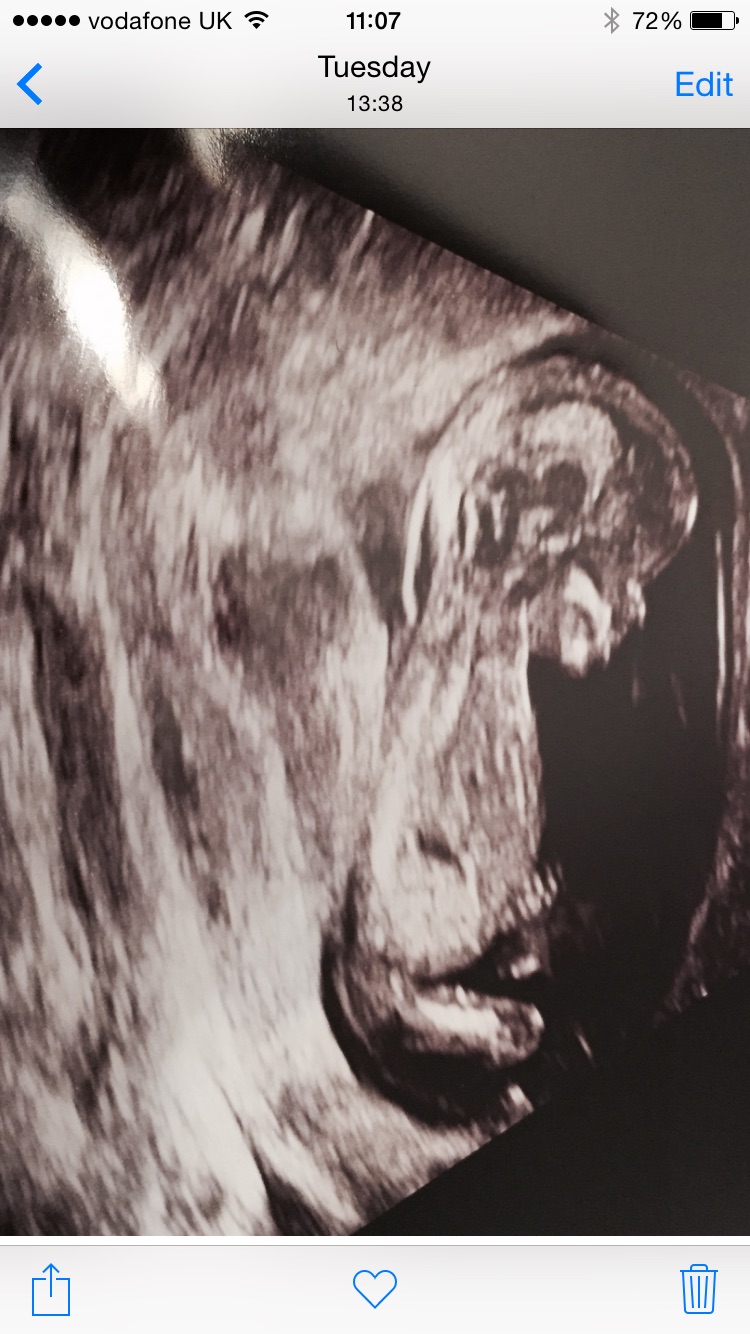

Here is another one, but you can't see a nub...

Attachment 24070